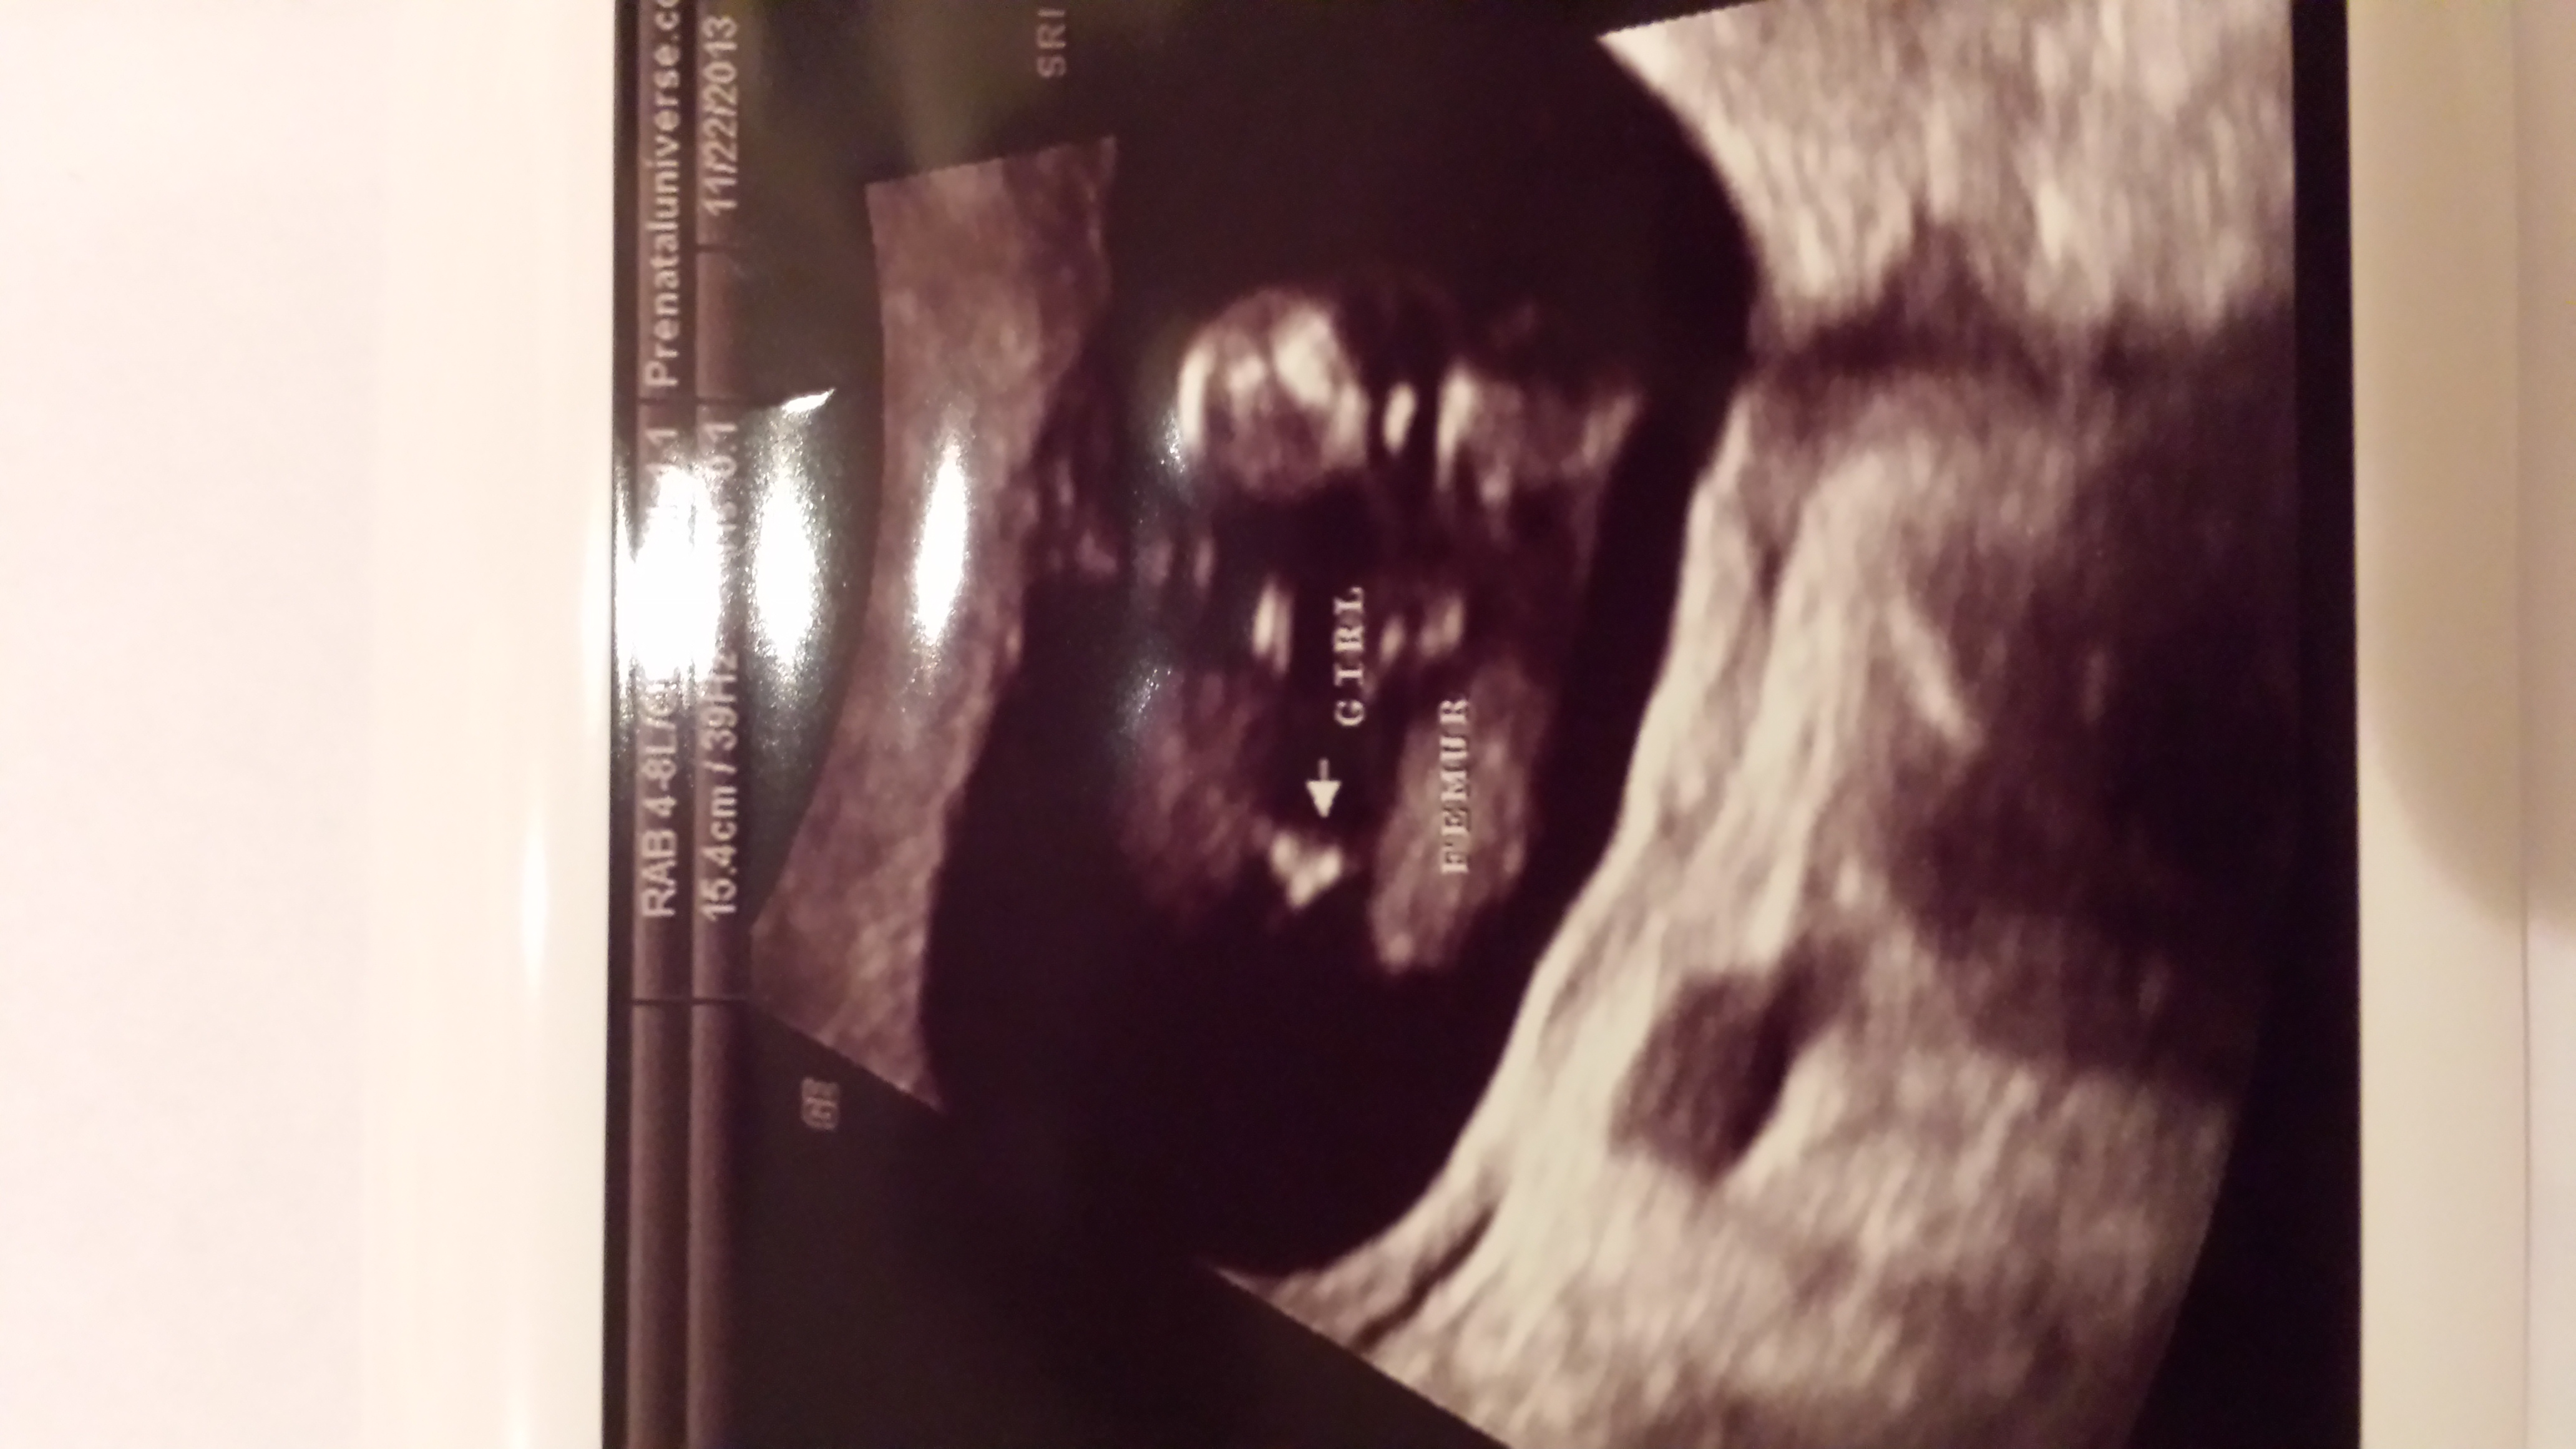

Had a 16w6d ultrasound yesterday...tech sounded 100% sure this was a girl. He said he didn't see any boy parts, and then when he snapped this pic, he said, "Yep, that's what I was looking for." My husband definitely thinks girl too. I have two boys, and their pics didn't look like this, but I'm just not convinced it's girl!

I would so appreciate your thoughts! Thank you so much!Attachment 15397